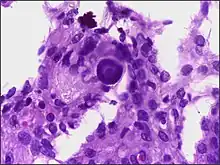

Pathophysiology

- A woven architectural pattern

- Psammoma bodies (spheroid calcifications)

- Syncytial cells (having indistinct cell membranes) with eosinophilic (pink) cytoplasms

- Round uniform nuclei

- Whorls (concentric cell arrangements)[15]

Histologically, meningioma cells are relatively uniform, with a tendency to encircle one another, forming whorls and psammoma bodies (laminated calcific concretions).[18] As such, they also have a tendency to calcify and are highly vascularized.